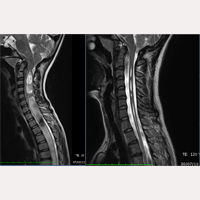

原發性脊柱側彎

巴塞隆納Chiari畸形&脊髓空洞症&脊柱側彎研究所

自1993年10月到今天,研究所已經有超過2000多位脊髓空洞症、Chiari I氏畸形、脊柱側彎患者接受終絲系統®醫療法(FILUM-SYSTEM®)的手術。